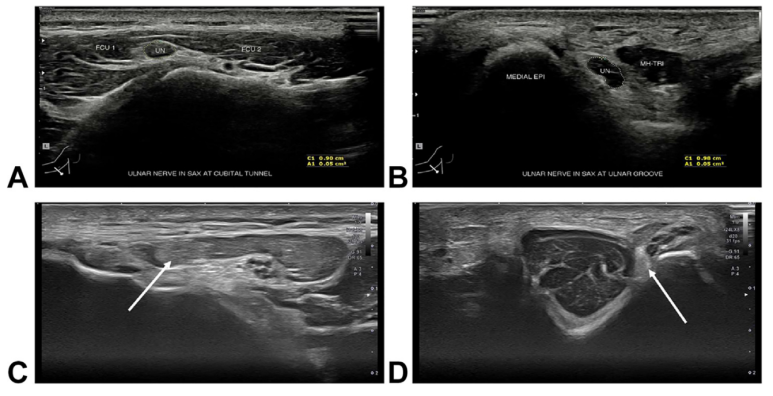

초음파, 진단 뿐만 아니라 치료까지 그래서 이 최신 논문은 근전도 검사 외에

'고해상도 초음파 검사'의 중요성을 강조합니다.

초음파는 *신경이 부어있는지, *원래 있어야 할 자리에서 벗어나있지는 않은지,

약 20%에서 발견되는 비정상적인 '주관근'이* 누르고 있지는 않은지 실시간으로 확인할 수 있습니다. 또한, 실시간으로 팔꿈치를 구부렸다가 펴면서 동적검사가 가능하기 때문에 (dynamic scan) 신경의 포착 범위를 구체적으로 찾아낼 수 있습니다. 심지어 근전도 검사가 정상인 환자들의 문제도 초음파는 잡아낼 수 있죠.